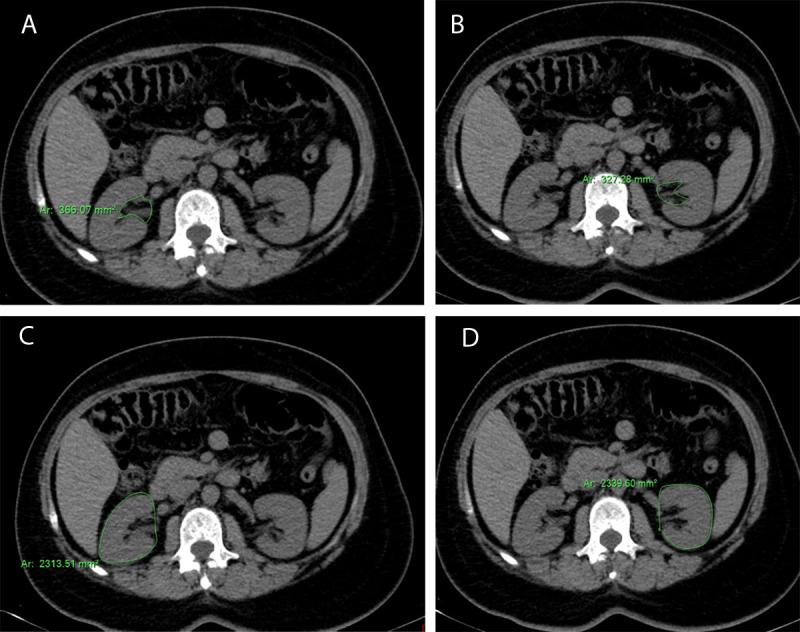

This cross-sectional study included two groups; the patients' group including 40 cases presented with a history of primary essential hypertension and the control group including 40 cases. The average of the surface area of the two kidneys as well as the average of the surface area of sinus fat was measured in the control and patient subgroups and was correlated with the presence and grading of essential hypertension as well as body mass index.

There was a significant correlation between the presence and grading of essential hypertension with prominent renal sinus fat. There was a significant correlation between the average surface area of kidneys and surface area of sinus fat in overweight and obese groups than in the control group (P < 0.01).

https://cdn.ncbi.nlm.nih.gov/pmc/blobs/a98e/9541188/8bf62a02d9cc/jbsr-106-1-2776-g1.jpg